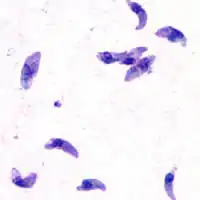

| T. gondii tachyzoites | |

Acute toxoplasmosis is often asymptomatic in healthy adults.[13][14] However, symptoms may manifest and are often influenza-like: swollen lymph nodes, headaches, fever, and fatigue,[15] or muscle aches and pains that last for a month or more. It is rare for a human with a fully functioning immune system to develop severe symptoms following infection. People with weakened immune systems are likely to experience headache, confusion, poor coordination, seizures, lung problems that may resemble tuberculosis or Pneumocystis jiroveci pneumonia (a common opportunistic infection that occurs in people with AIDS), or blurred vision caused by severe inflammation of the retina (ocular toxoplasmosis).[15] Young children and immunocompromised people, such as those with HIV/AIDS, those taking certain types of chemotherapy, or those who have recently received an organ transplant, may develop severe toxoplasmosis. This can cause damage to the brain (encephalitis) or the eyes (necrotizing retinochoroiditis).[16] Infants infected via placental transmission may be born with either of these problems, or with nasal malformations, although these complications are rare in newborns. The toxoplasmic trophozoites causing acute toxoplasmosis are referred to as tachyzoites, and are typically found in bodily fluids.[17][18]

While rare, skin lesions may occur in the acquired form of the disease, including roseola and erythema multiforme-like eruptions, prurigo-like nodules, urticaria, and maculopapular lesions. Newborns may have punctate macules, ecchymoses, or "blueberry muffin" lesions. Diagnosis of cutaneous toxoplasmosis is based on the tachyzoite form of T. gondii being found in the epidermis.[31] It is found in all levels of the epidermis, is about 6 by 2 μm and bow-shaped, with the nucleus being one-third of its size. It can be identified by electron microscopy or by Giemsa staining tissue where the cytoplasm shows blue, the nucleus red.[32]

In its lifecycle, T. gondii adopts several forms.[33] Tachyzoites are responsible for acute infection; they divide rapidly and spread through the tissues of the body. Tachyzoites are also known as "tachyzoic merozoites", a descriptive term that conveys more precisely the parasitological nature of this stage.[34] After proliferating, tachyzoites convert into bradyzoites, which are inside latent intracellular tissue cysts that form mainly in the muscles and brain. The formation of cysts is in part triggered by the pressure of the host immune system.[35] The bradyzoites (also called "bradyzoic merozoites") are not responsive to antibiotics. Bradyzoites, once formed, can remain in the tissues for the lifespan of the host. In a healthy host, if some bradyzoites convert back into active tachyzoites, the immune system will quickly destroy them. However, in immunocompromised individuals, or in fetuses, which lack a developed immune system, the tachyzoites can run rampant and cause significant neurological damage.[33]